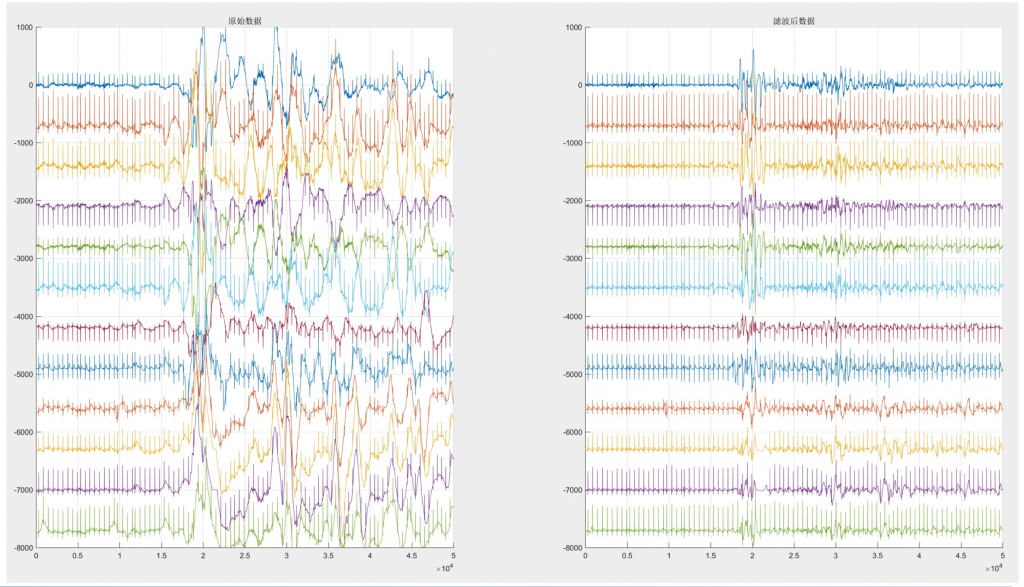

医疗滤波器性能展示

医疗滤波器性能展示